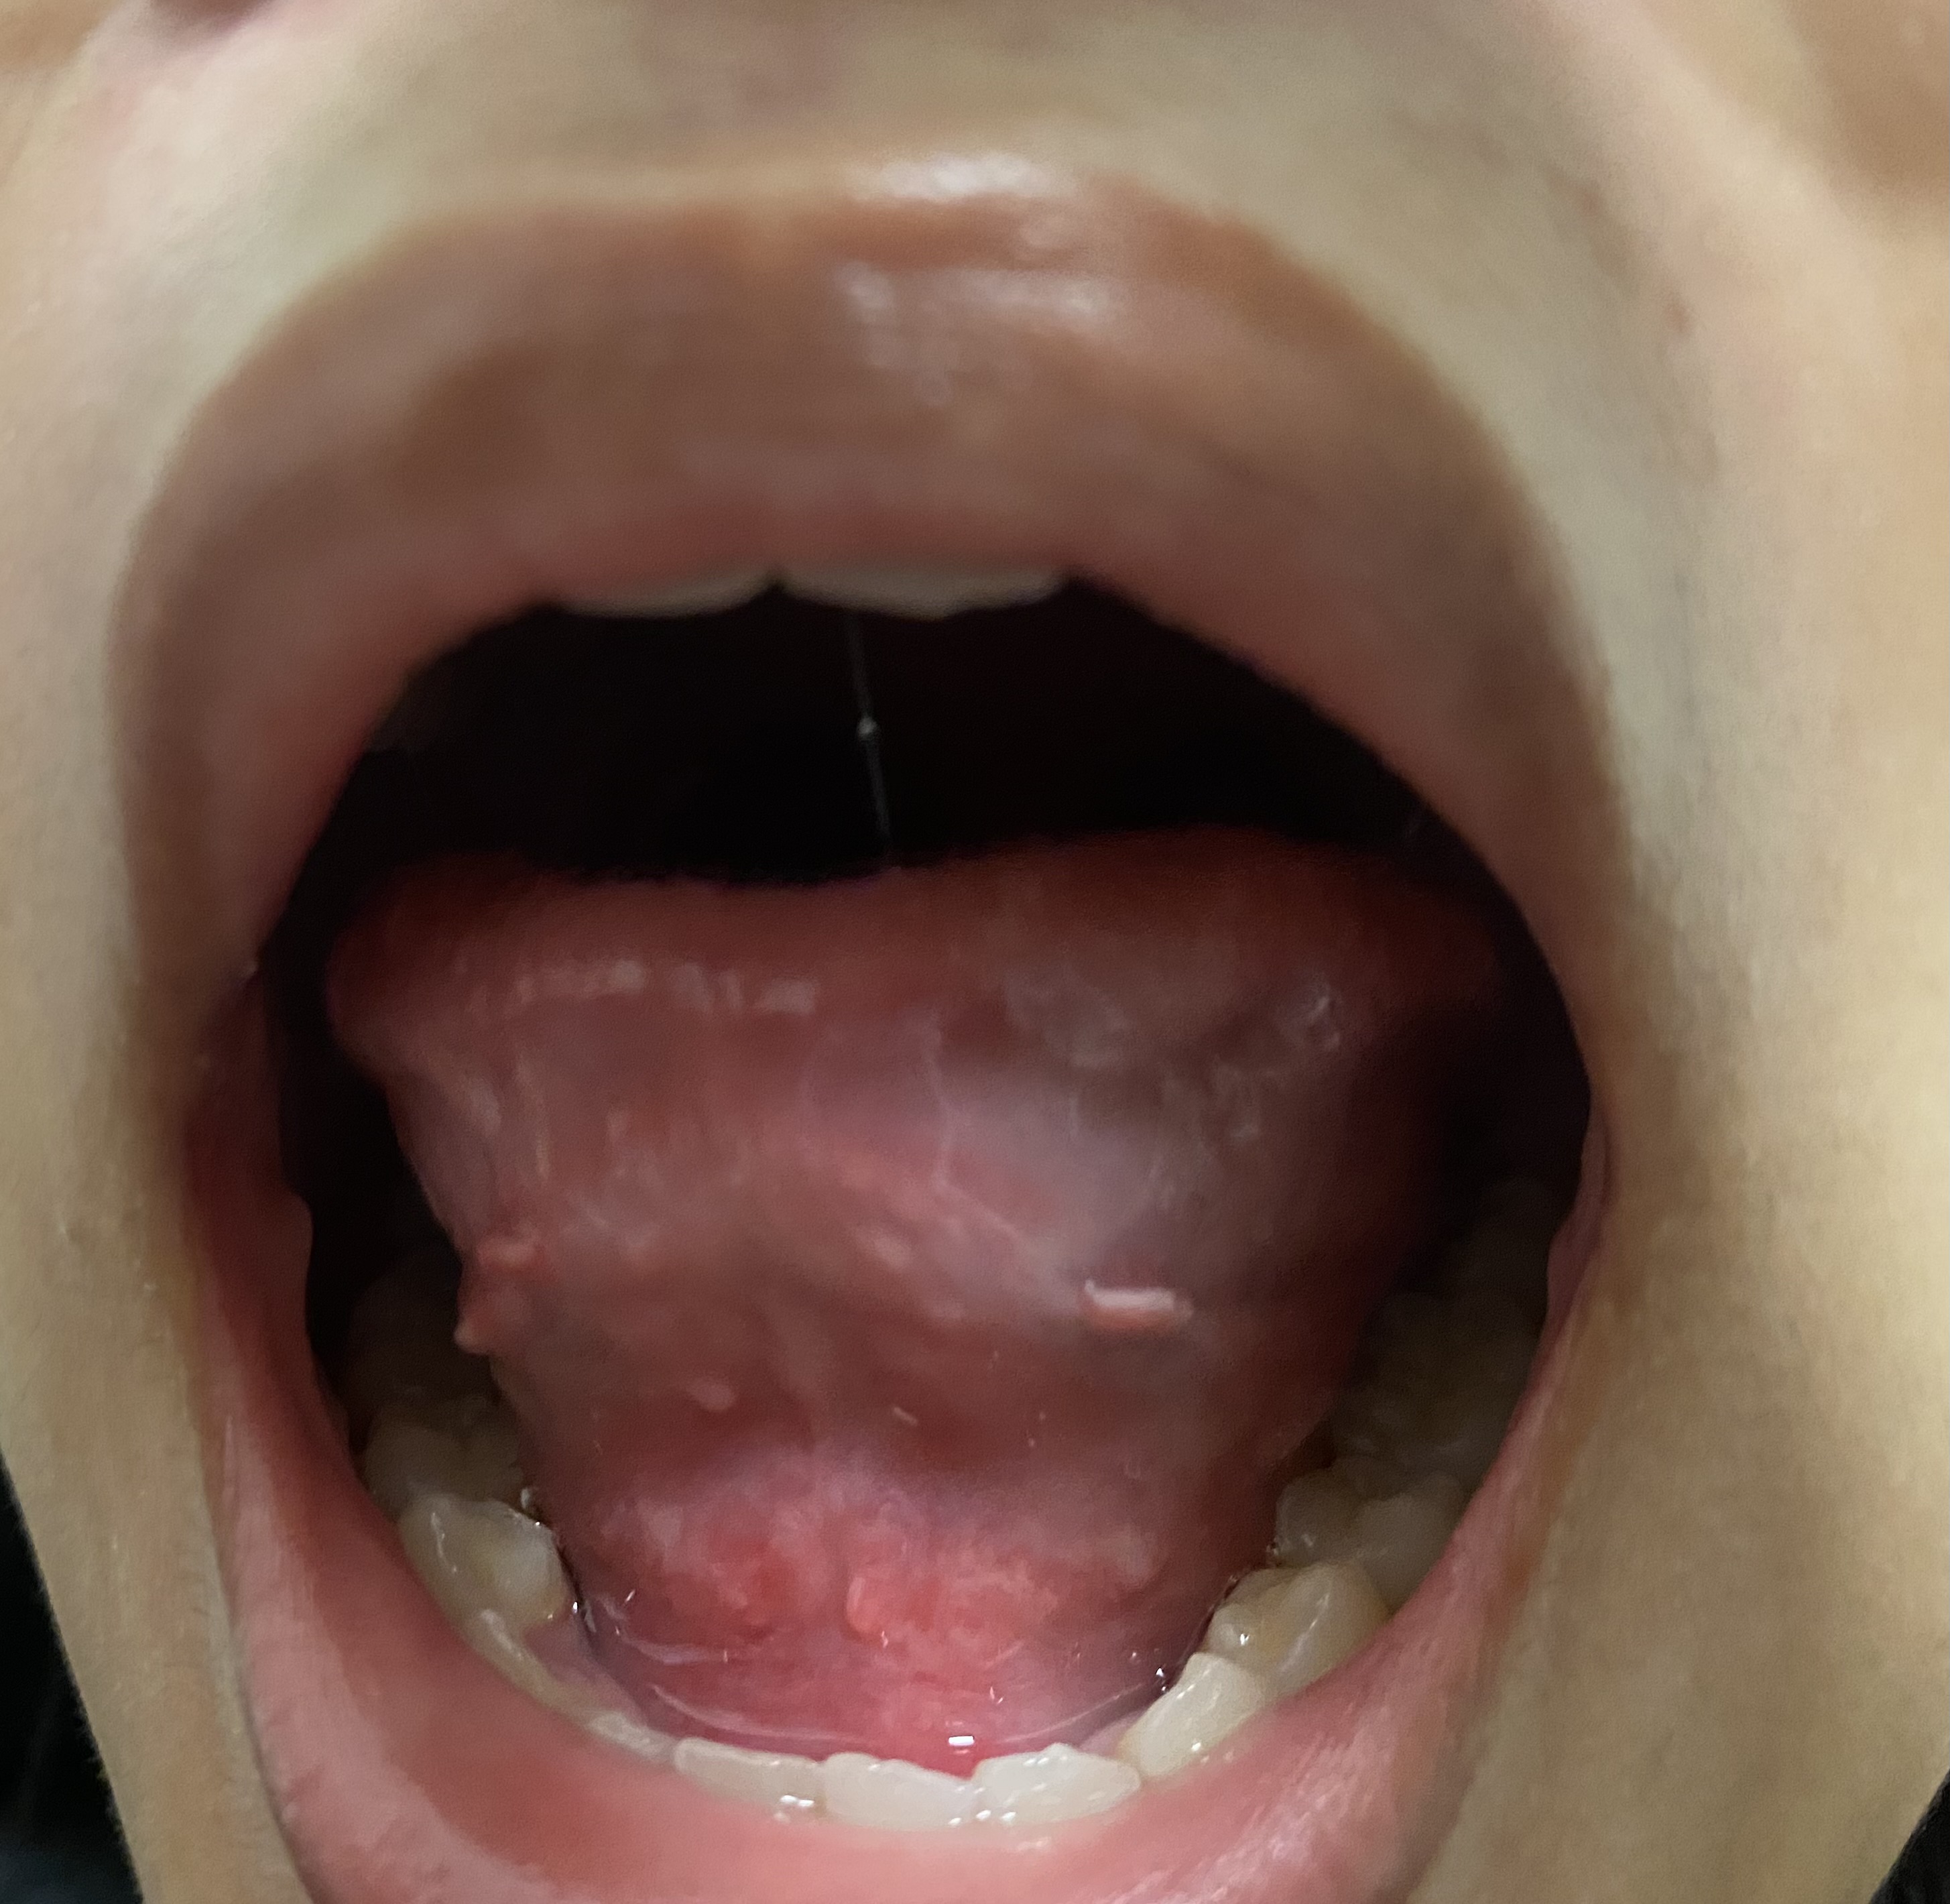

https://haamor.com/media/create_topic/20250420213709.jpeg

ช่วงนี้รู้สึกแปรงฟันแล้วแสบปากมากๆเลยค่ะ แสบจนน้ำตาไหลเลยก็มี แปรงฟันเลือดออกทุกครั้งเลยด้วยค่ะ กินผลไม้พวกสตอเบอรี่ก็แสบค่ะ ตอนไม่ได้กินอะไรก็รู้สึกเจ็บๆอยู่นิดหน่อยค่ะ พอมาลองส่องดูแล้วเจอเหมือนเนื้อๆงอกออกมาแบบในรูปเลยอะค่ะคุณหมอ อยากทราบว่ามันเกิดจากอะไรได้บ้าง แล้วต้องรักษายังไงได้บ้างคะ

ติ่งงอกที่เห็นเป็นปกติครับ

แต่ใต้ลิ้นมีฝ้าขาวผิวอักเสบ อาจเกิดจากแพ้อาหารหรือขาดวิตามิน เบื้องต้นลองใช้ kamillosan M พ่นวันละสามครั้งครับ ถ้าเจ็ดวันแล้วยังไม่ดีขึ้นให้ไปพบแพทย์หูคอจมูกครับ